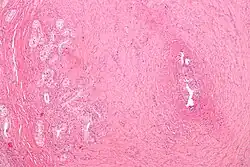

![]() Obraz mikroskopowy vasitis nodosa po zabiegu przywrócenia ciągłości nasieniowodu | |

Vasitis nodosa – powikłanie po wazektomii pojawiające się w około 66% przypadków[1] (50%[2]) w okresie do kilku miesięcy po zabiegu[2].

Powikłanie ma postać guzkowatego zgrubienia nasieniowodu o niezłośliwym, łagodnym charakterze, z kanalikowatymi mikroodgałęzieniami penetrującymi okoliczną tkankę[2]. Podczas rozpoznania może być pomylone z niskozróżnicowanym gruczolakorakiem[3].